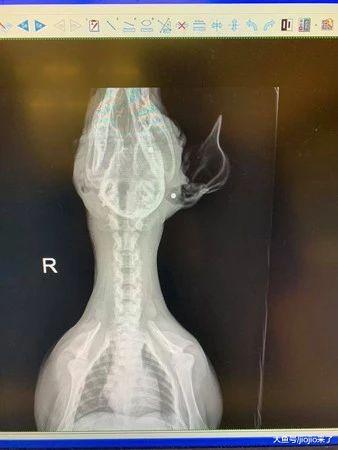

小奶狗遭变态连射三枪奇迹生还!获救后居然还有心思撒娇……

美国当地时间15日晚 , 加利福尼亚州科斯菲尔德贝克尔斯菲市的街道上传来了几声枪响 , 一名胆大的女子走了出来 。 当她来到一处汽车附近时 , 隐约听到阵阵哭泣声……